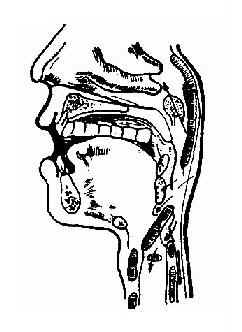

异物咽入咽部后,首先感到咽部刺痛,吞咽时加重。如病人主诉疼痛点在舌骨平面以上,常与异物所在处相符合。如主诉疼痛点位于甲状软骨下缘,分不清左右侧,异物可能已进入食管。若异物虽已自动脱落,但粘膜已被擦伤,局部疼痛症状仍可持续1~2d,其疼痛程度应逐日减轻消失(图11-5)。

图11-5 咽异物常见位置

根据病史、症状及检查不难诊断。咽部异物多见于扁桃体隐窝、舌根、会厌谷和梨状窝等部位。细小鱼刺常似唾液粘丝,容易混淆不清,应反复仔细检查。